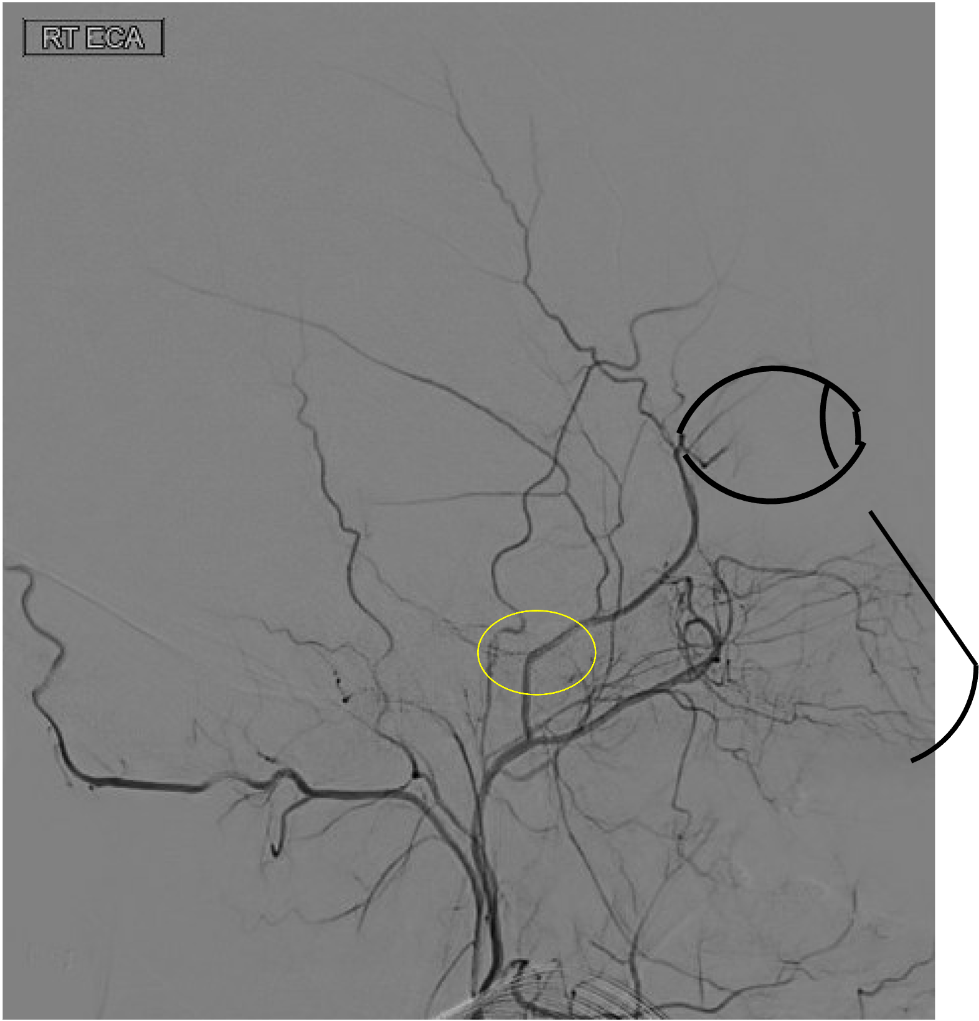

On this lateral view L ECA injection, name the vessel at the white arrow, which is the route of collateral between the ECA and ICA (yellow arrow) in this patient with longstanding ICA occlusion.

White arrow is the Ophthalmic artery-- here, likely collaterals from the ECA (through the internal maxillary artery --> ethmoidal artery) collateralize with the ICA through retrograde filling of the Ophthalmic